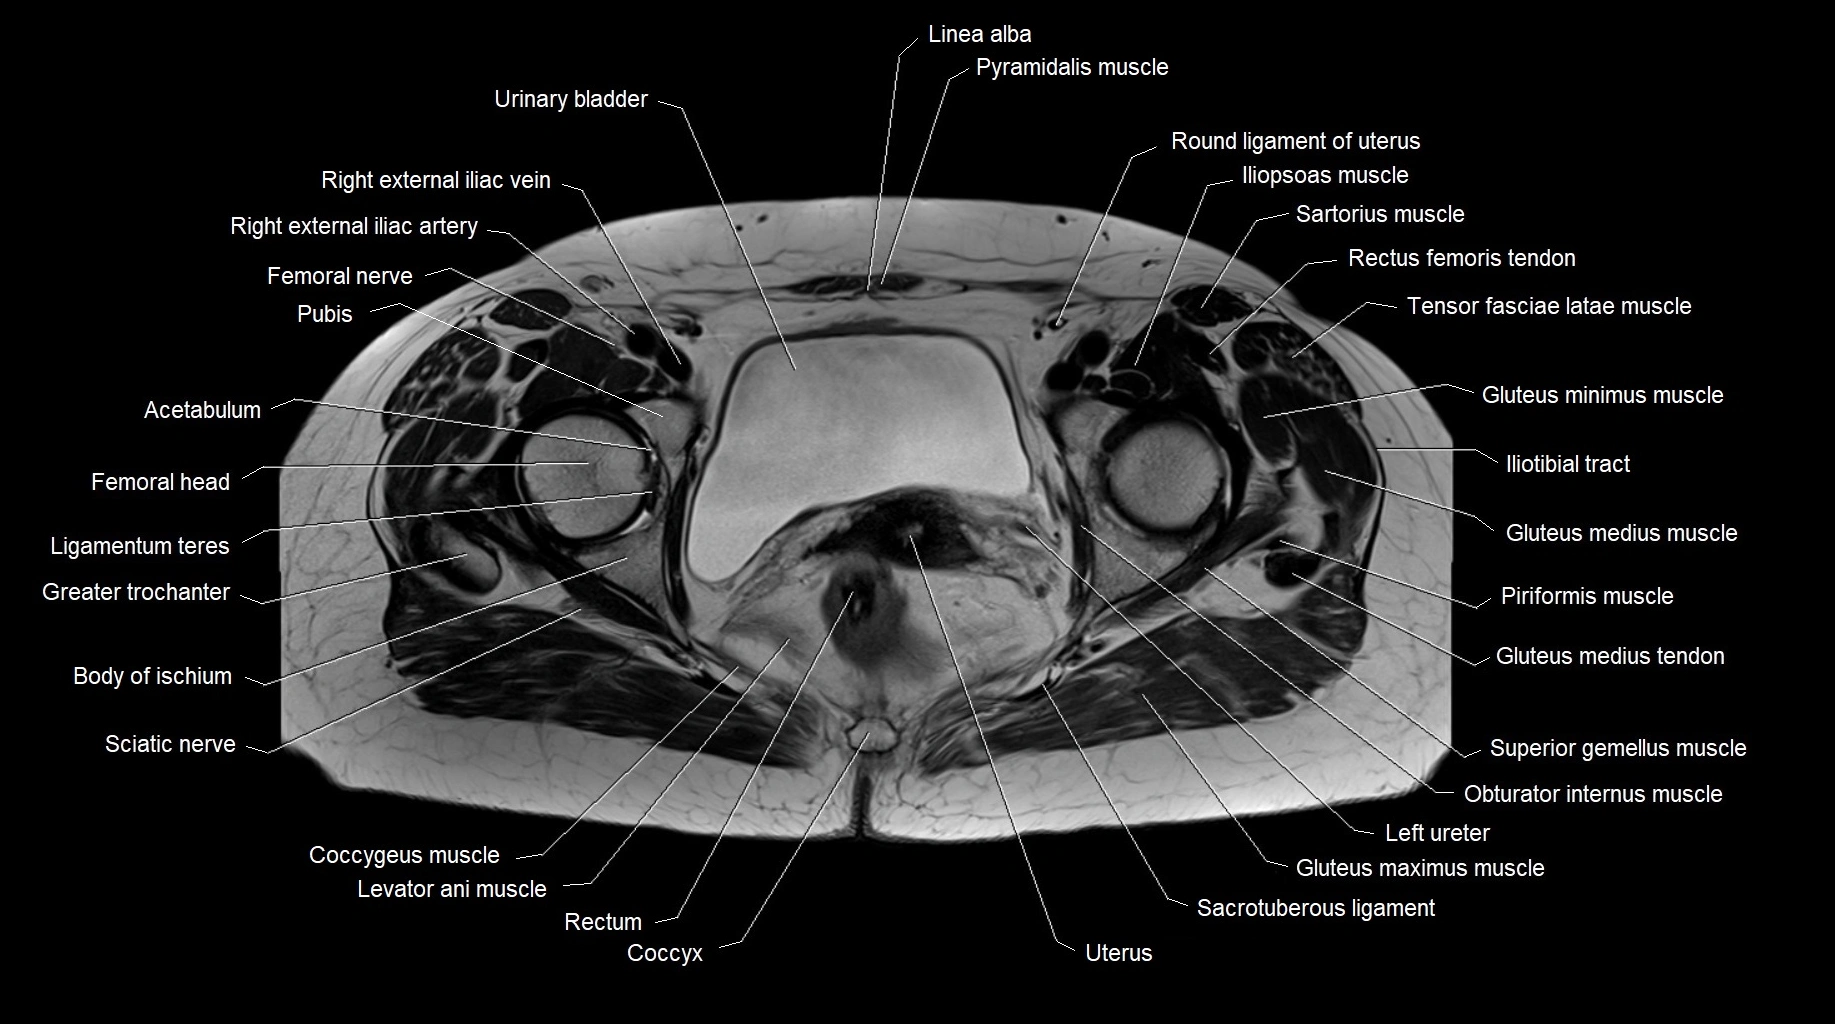

- Co (Coccyx)

- Coccygeus muscle

- Coccyx

- Gluteus medius tendon

- Head of femur

- Greater trochanter

- Iliotibial tract

- Levator ani muscle

- Ligamentum teres (ligament of the head of femur)

- Linea alba

- Obturator internus muscle

- Piriformis muscle

- Pyramidal muscle (pyramidalis muscle)

- Rectum

- Round ligament of uterus

- Sacrotuberous ligament

- Sciatic nerve

- Superior gemellus muscle

- Tensor fasciae latae muscle

- Urinary bladder

- Uterus